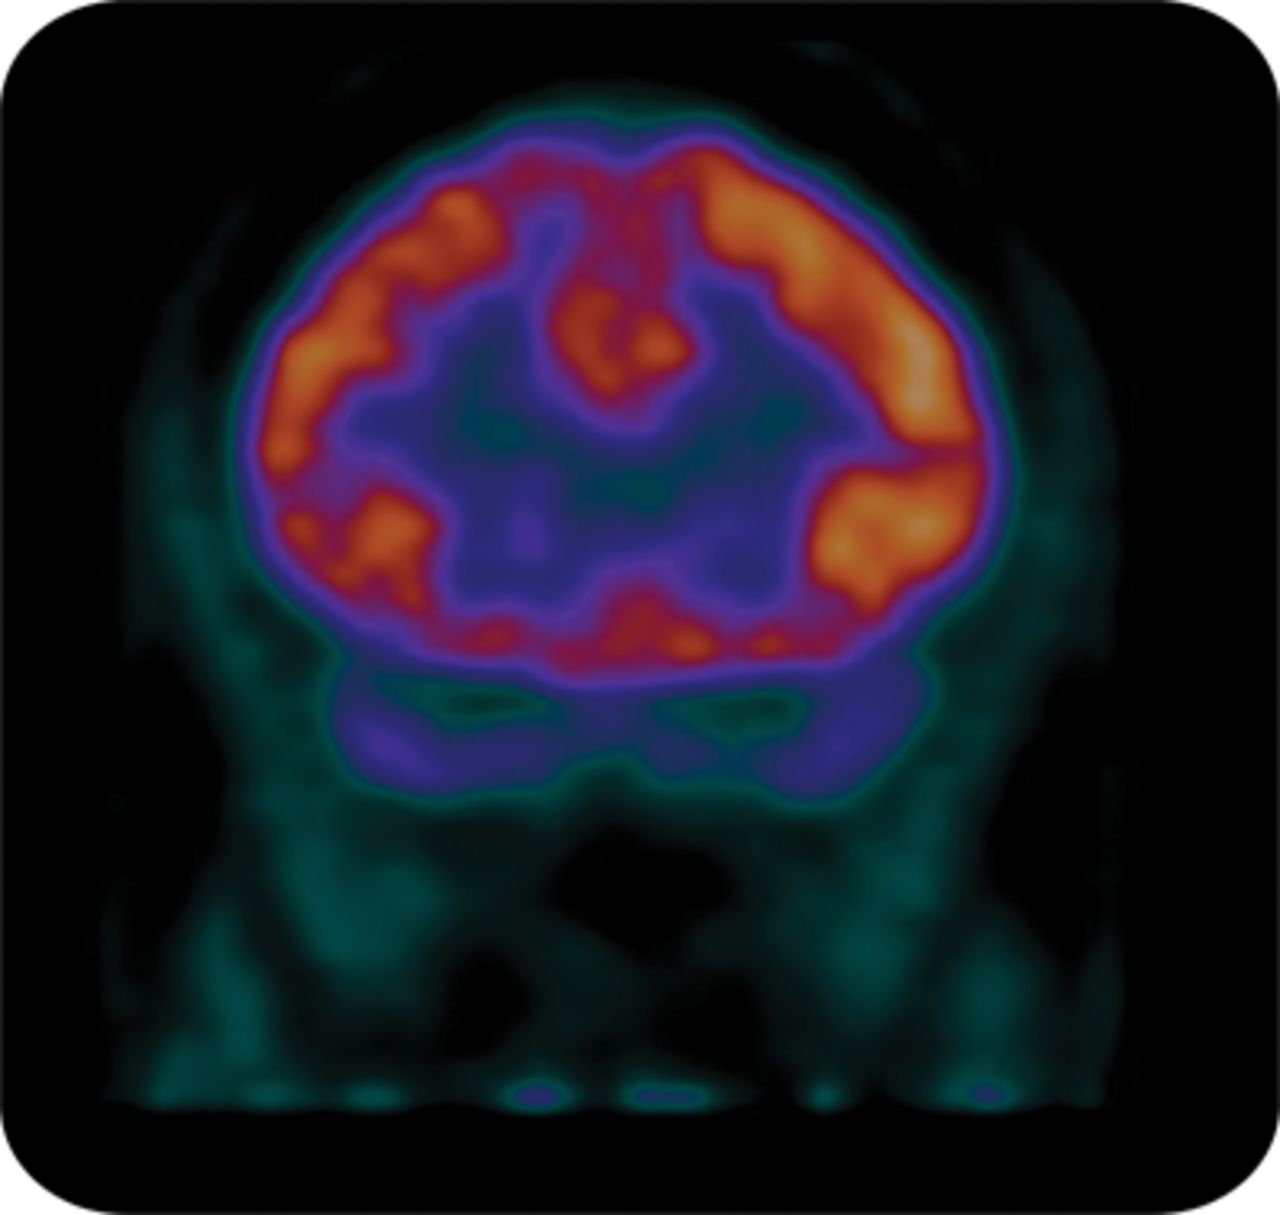

一个48岁的女人是医学上的40年历史评价耐火材料缺失和广义tonic-clonic发作。神经系统检查和大脑MRI是正常的。快速清醒发作脑电图显示广义棘波复杂,总是对半球最大(图1)。换气过度引起的短暂行为被捕陪同广义EEG棘波活动。发作脑部PET扫描显示弥漫性右半脑代谢减退(图2)。布卢姆1创造了这个词的半球癫痫表示癫痫综合征在13个病人从数据库超过25000人。这种罕见的条件模拟难治性特发性全身性癫痫,除了一贯不对称脑电图痫性活动。